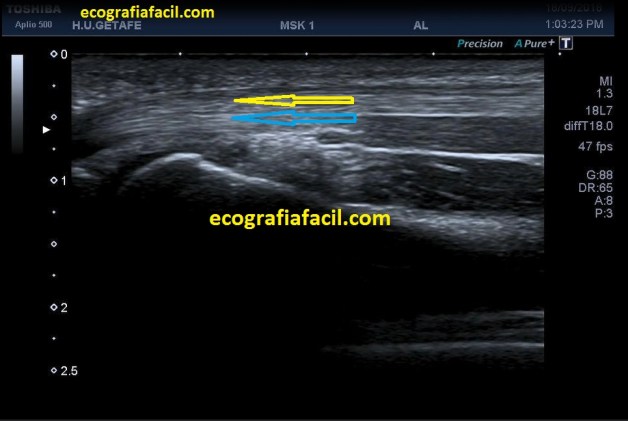

Criptorquidia: El testículo no descendido es una de las anomalías genitourinarias más comunes en niños. La mayoría de los testículos no descendidos son palpables y se localizan en el canal inguinal. Su aspecto ecogénico es normal, salvo si son vistos en la edad adulta, que pueden ser más pequeños y de ecogenicidad alterada. Objetivamente no van a estar en las bolsas y los vamos a encontrar donde marca el picto de la imagen 12. En ocasiones necesitan tratamiento quirúrgico. La flecha amarilla fina y alargada te marca la profundidad anómala debido a la piel y el tejido celular subcutáneo típico de la región inguinal, observa como cambia esta imagen respecto de cualquiera de las anteriores con los testes en sus bolsas.